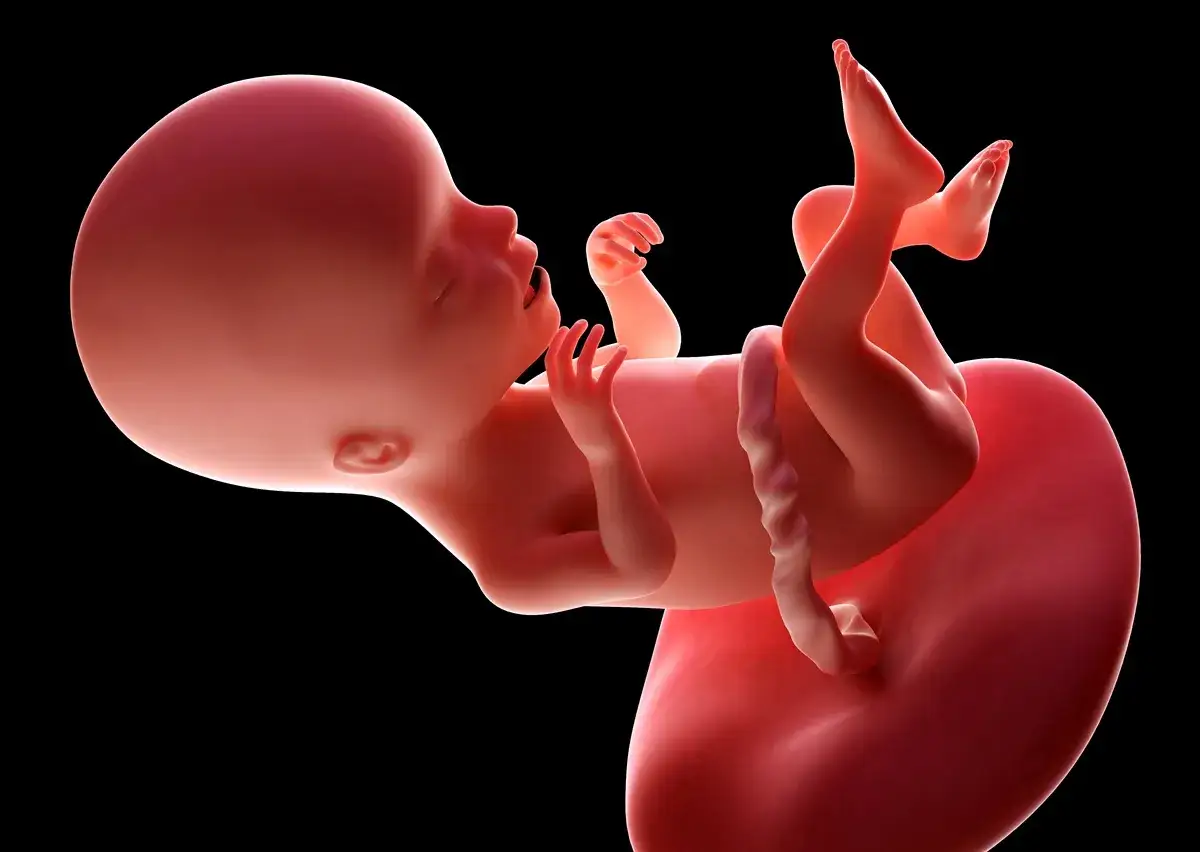

W 17. tygodniu ciąży Twój maluszek dynamicznie rośnie i rozwija się w zawrotnym tempie. Obecnie ma już około 13 cm długości (mierząc od czubka głowy do pięt) i waży w granicach 140-150 gramów. Aby łatwiej sobie to wyobrazić, pomyśl o nim jak o wielkości dużej gruszki lub sporej cebuli. W tym czasie dziecko zaczyna również gromadzić tkankę tłuszczową, tzw. tłuszcz brunatny, który będzie kluczowy dla utrzymania odpowiedniej temperatury ciała po narodzinach.

Jednym z najważniejszych procesów zachodzących w tym tygodniu jest kostnienie szkieletu. Chrząstki, które do tej pory stanowiły podstawę jego struktury, zaczynają twardnieć, przekształcając się w prawdziwe kości. Skóra dziecka jest jeszcze niezwykle cienka i przezroczysta, co sprawia, że pod nią widać naczynia krwionośne.

Twój maluszek intensywnie ćwiczy również odruchy, które będą mu niezbędne po urodzeniu. W 17. tygodniu płód aktywnie połyka płyn owodniowy, co jest doskonałym treningiem dla układu pokarmowego. Ćwiczy także odruch ssania, co jest kluczowe dla karmienia piersią. To fascynujące, jak natura przygotowuje go do życia poza Twoim łonem!

Co więcej, w tym tygodniu następuje znaczący rozwój zmysłu słuchu. Uszy dziecka stają się coraz bardziej wrażliwe i zdolne do odbierania dźwięków z zewnątrz. Możesz już zacząć do niego mówić, śpiewać czy puszczać spokojną muzykę. Maluszek z pewnością to doceni, a to buduje wspaniałą więź między Wami.